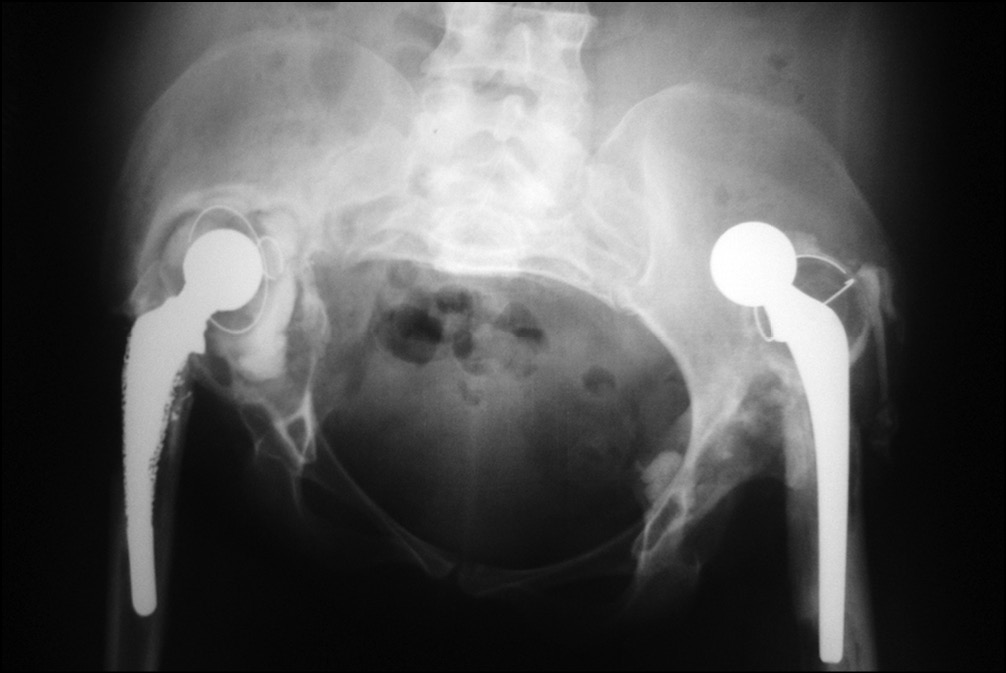

Рис. 5. Рентгенограмма таза при контроле в 2005 г.

В 2007 г. появились резкие боли в области левого тазобедренного сустава, укорочение левой нижней конечности (рис. 6).

Рис. 6. Рентгенограмма таза при поступлении в клинику в 2007 г.

На контрольных рентгенограммах выявлен дефект вертлужной впадины типа IIIA и дефект бедренной кости типа IIIB по классификации W.G. Paprosky. В 2012 г. по поводу нестабильности тотального эндопротеза левого тазобедренного сустава выполнено ревизионное эндопротезирование с использованием антипротрузионного кольца ЭСИ (фирма Эндосервис) с цементной чашкой и бедренного компонента типа Цваймюллера, дефект бедренной кости восстановлен с применением свежезамороженного кортикального трансплантата. (рис. 7 и 8).